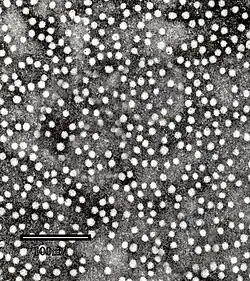

HBsAg self-assembles into viral shells even when no contents are present. Such an empty shell is called a virus-like particle or a small spherical subviral particle.[1]

HBsAg made through recombinant DNA is used to make the hepatitis B vaccine. It has a very good efficacy of about 95%,[6] with protection lasting for more than 30 years, even after the anti-HbsAg antigen titers have fallen.[7]

The RTS,S also makes use of HBsAg. It is a mixture of a version of malaria surface antigen grafted to HBsAg (RTS) and ordinary HBsAg (S), both made through recombinant DNA. Much like ordinary HBsAg, these two are able to assemble into virus-like particles that are soluble in water.[8]